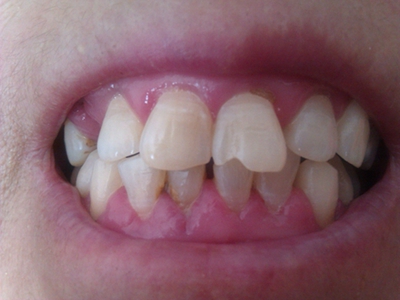

牙龈炎是发生于牙龈组织的炎症,患者可出现牙龈出血伴肿胀、发红、正常形态改变和偶尔不适等症状。本病主要由口腔卫生状况差导致,包括口腔不洁、牙菌斑等,诊断依据临床检查,治疗包括专业牙齿清洁和加强家庭口腔卫生。

牙龈炎可先引起牙齿与牙龈之间的沟(龈沟)加深,然后牙龈充血,炎症围绕一个或多个牙齿,伴牙龈乳头肿胀和易出血。一般无痛,可自行消退,也可维持轻度炎症数年。